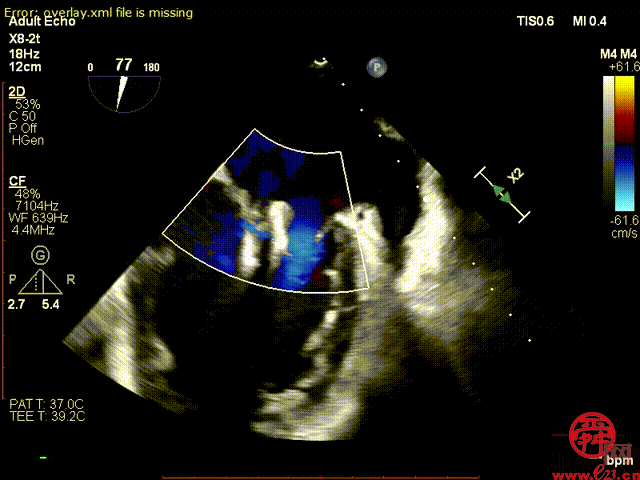

该患者为进一步治疗就诊于齐鲁医院心血管内科,初步诊断为酒精性心肌病、二尖瓣反流(重度)、射血分数减低型心力衰竭、心功能Ⅲ级(NYHA分级)、心律失常、短阵室性心动过速、冠状动脉粥样硬化等。术前心脏彩超经胸超声检查提示,二尖瓣重度反流4+,二尖瓣反流束宽度1.87cm,缩流颈宽度VC=0.7cm,有效反流口面积(EROA)=0.47,二尖瓣瓣口面积5.0cm。

术中,患者全麻后,在经食道超声和DSA的引导下,经股静脉建立路径,穿刺房间隔,瓣膜夹通过输送系统送入左心房,顺利到达二尖瓣病变区域。在经食道超声和DSA的辅助下,术者通过反复评估二尖瓣反流位置、抓捕位置、反流程度、巧妙夹合,在A2/P2区植入2枚DragonFly夹子。术后,患者反流程度从4+转至1+,手术取得成功。